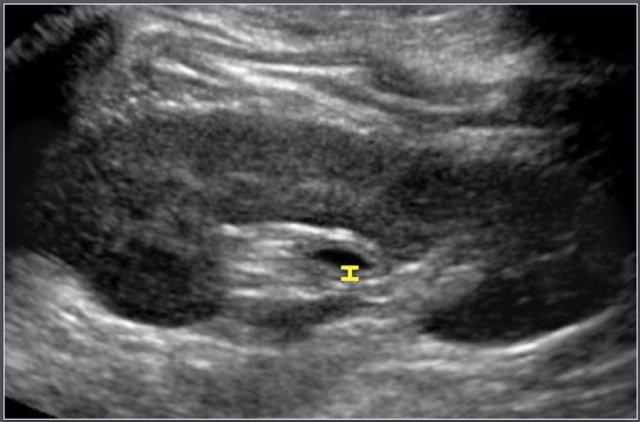

Độ dày thành hệ thống thu thập nước tiểu

Vật liệu và Phương pháp

Siêu âm được thực hiện trên 48 hệ thống thu thập nước tiểu của 24 trẻ em khỏe mạnh (tuổi từ 3 ngày đến 12,6 tuổi).

Thành hệ thống thu thập nước tiểu quan sát được ở tất cả các thận, với độ dày dao động từ 0 (không nhìn thấy) đến 0,8 mm.

Độ dày thành ≥ 1 mm được coi là bất thường.

Các nguyên nhân thường gặp gây dày thành hệ thống thu thập nước tiểu bao gồm:

- Nhiễm khuẩn đường tiết niệu (UTI)

- Giãn đường tiết niệu từng đợt (ví dụ: trào ngược bàng quang-niệu quản)

- Giãn đường tiết niệu gần đây hoặc đã hồi phục